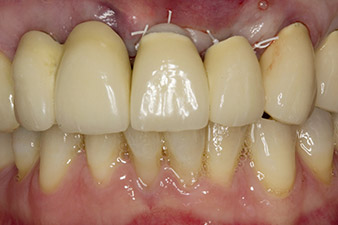

A 67-year-old patient presented with splinted crowns in the maxilla requiring replacement. Following the extraction of teeth 21 and 22, the plan is to insert implants as new bridge abutments. The sites will be prepared with the new W&H Implantmed implantology motor and the stability measured with the integrated W&H Osstell ISQ module.

When the patient first presented, teeth 21, 22 and 23 had been restored with splinted crowns, now 19 years old, which were bonded to the implants at positions 12/11 by an attachment (cf. Fig. 2).

Tooth 23 displayed a horizontal-coronal fracture and was restored with a post and core build-up for the temporary restoration. The plan was to place a zirconium oxide bridge on the existing implants at positions 12 and 11 and to place two new implants at positions 22 and 23.